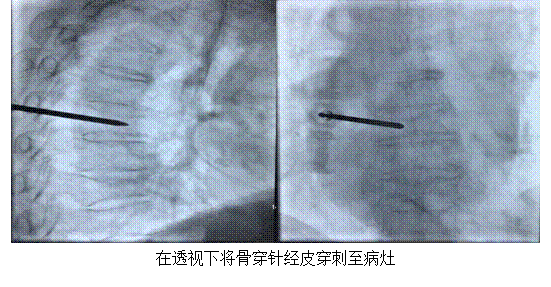

骨轉(zhuǎn)移瘤是惡性腫瘤的常見(jiàn)并發(fā)癥,其中脊柱轉(zhuǎn)移瘤發(fā)生率可高達(dá)30%~50%。最易發(fā)生脊柱轉(zhuǎn)移的腫瘤包括肝癌、乳腺癌、肺癌、前列腺癌等。脊柱轉(zhuǎn)移瘤嚴(yán)重影響患者生活治療,其主要表現(xiàn)為難以忍受的疼痛、病理性骨折、神經(jīng)根或脊髓壓迫癥狀,嚴(yán)重時(shí)會(huì)導(dǎo)致患者癱瘓。經(jīng)皮椎體成形術(shù)(Percutaneous Vertebroplasty,PVP),也叫經(jīng)皮骨水泥成形術(shù),是由 Deramond和Galibert兩位學(xué)者首次提出,其原理是在高清晰度影像設(shè)備導(dǎo)引下用骨穿針經(jīng)皮通過(guò)椎弓根或椎弓根外側(cè),實(shí)時(shí)透視下向病變椎體內(nèi)注入聚甲基丙烯酸甲酯 (PMMA),以達(dá)到提高脊柱穩(wěn)定性、恢復(fù)并增加椎體力學(xué)強(qiáng)度和剛度的目的。